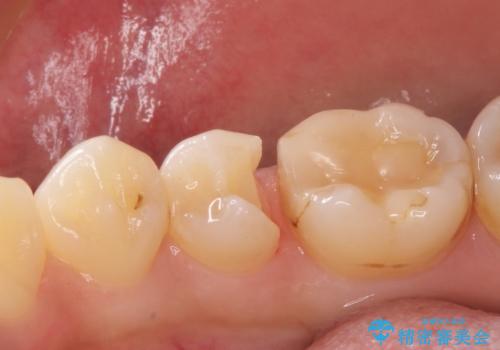

- 歯が欠けて、そこに食べ物が詰まるとのことで来院されました。

虫歯が大きく進行していました。

顕微鏡下で丁寧に虫歯を取り除き、セラミックインレーによる修復治療を行いました。

虫歯が大きく広がっていましたが、顕微鏡を使って慎重に治療を行うことで、神経をとってしまうことなく治療することができます。